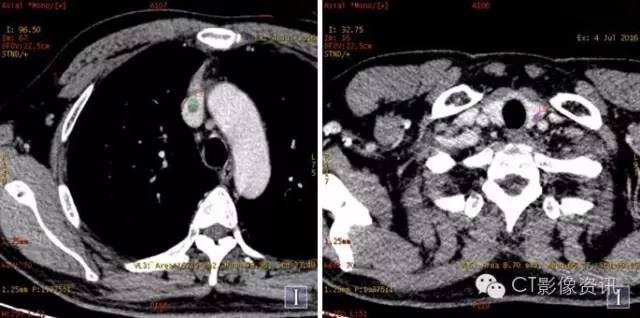

扫描方法 能谱平扫及两期增强扫描。病理已提示右上肺癌纵隔淋巴结转移;上腔静脉病灶为癌栓?血栓?左甲状腺病灶为转移?原发病灶? 常规平扫及静脉期

常规图像及碘基图均显示上腔静脉病灶明显强化。

常规平扫及强化两期

常规图像及碘基图显示病灶轻度强化。

右肺、上腔静脉及纵隔淋巴结病灶曲线斜率基本一致,而左甲状腺病灶能谱曲线与其明显不一致,综合CT平扫及强化各期特点以及病理结果,上腔静脉病灶考虑癌栓;左甲状腺病灶考虑甲状腺腺瘤(非转移病灶)可能大。